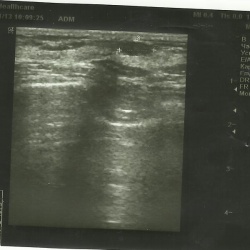

20.05.13. УЗИ мягких тканей. Лимфаденит. Молодая женщина пришла на обследования из-за болезненности в области шеи в подчелюстном треугольнике.Слева в области подчелюстного треугольника...